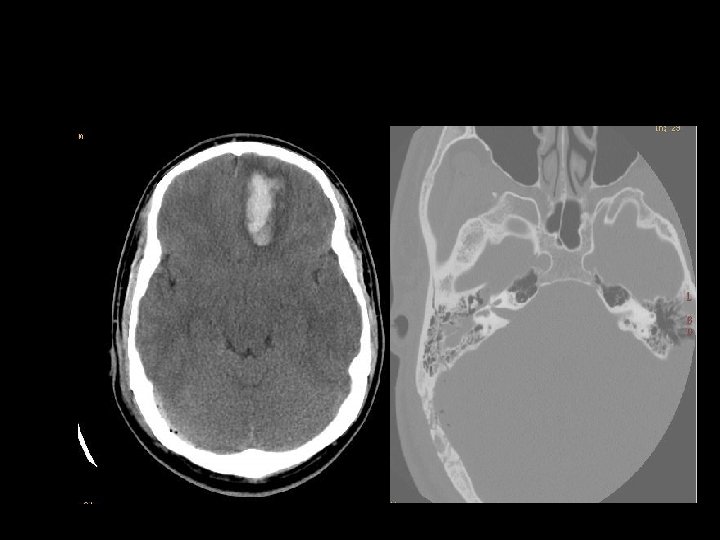

Intraparenchymal hematoma n Kumpulan darah fokal yang tersering timbul dari shear-strain injury pada pembuluh darah intraparenkim n Umumnya berlokasi pd frontotemporal white matter atau basal ganglia n Hematoma di dalam parenkim otak yang normal n DDx: DAI, hemorrhagic contusion

SUBDURAL HEMATOMA n Timbul antara dura dan arachnoid n Dapat melewati sutura n Timbul akibat disrupsi bridging cortical veins n Bentuk konkaf n Hipodens(hiperakut, kronis), isodens(subakut), hiperdens(akut)

EPIDURAL HEMATOMA n Berlokasi antara skull dan periosteum n Akibat laserasi arteri meningea media atau vena dural n Dibatasi oleh sutura n Bentuk lentiform / bikonveks